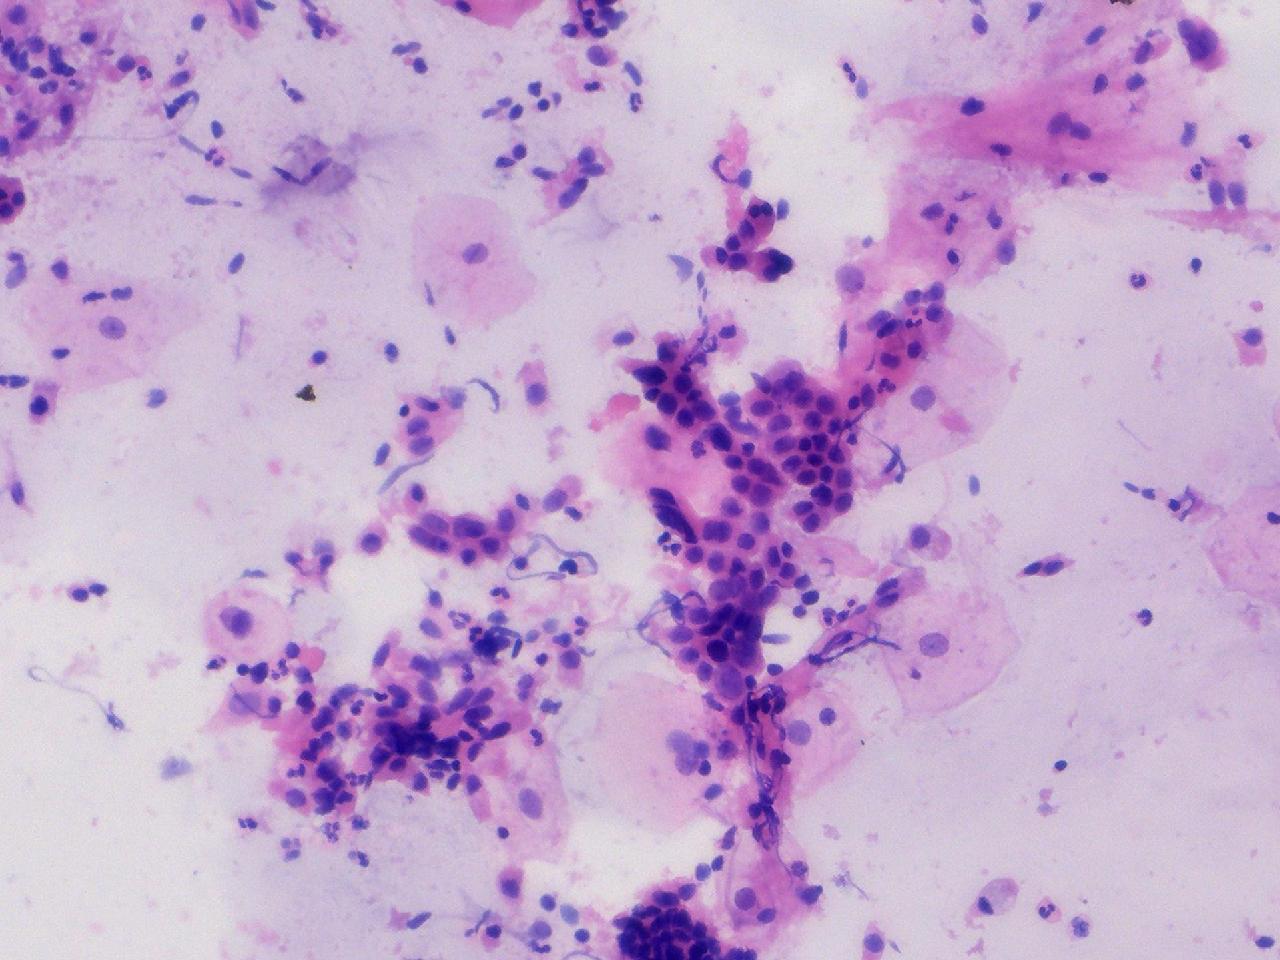

可见较多腺细胞。请教诊断。

性别

女

年龄

55岁

一般病史

绝经2年余,阴道淡血水3月余,子宫肌瘤10余年,HPV不详。

标本类型

妇科TCT

制片方法

离心后,沉降式制片

染色方法

NILM